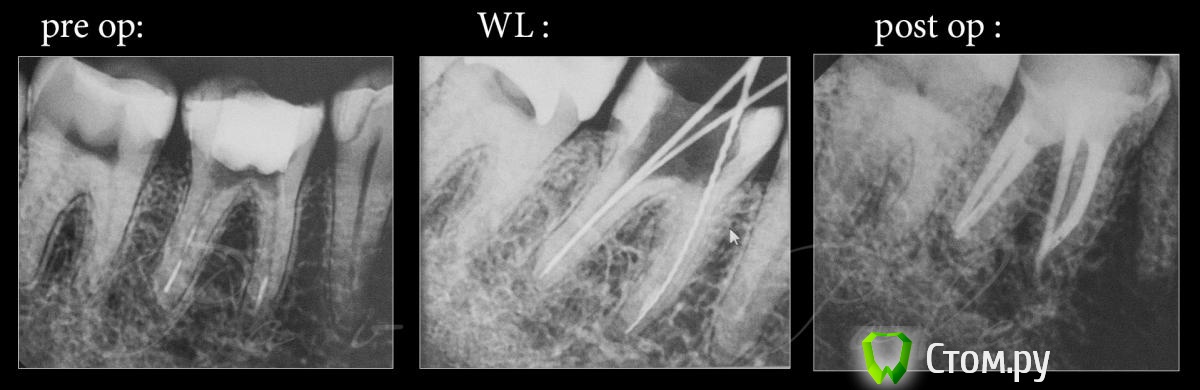

Lyuba Опубликовано 25 ноября, 2014 Автор Поделиться Опубликовано 25 ноября, 2014 (изменено) продолжение истории:периодонтитный 46 зуб был "перелечен".... с 25 сентября почти месяц простоял с антибиотиком, потом каласепт и пломбировка каналов. Прошел месяц после пломбировки (под микроскопом), зуб до сих пор ноет. причем такое ощущение, что ноют по очереди все зубы с 44 по 47.... на постукивание больше реагирует 46 зуб, реакции на холодное-горячее-сладкое нет, просто периодические ноющие боли. В 45 и 47 меняли пломбы (тоже месяц назад) кариеса нет, врач говорила, что пульпа "не вскрыта", но полость, конечно, глубокая, что и видно на рентгене. 44, 45 и 47 - "живые" зубы (проверено прибором). Отчего могут быть такие боли, как определить причину? не депульпировать же 44, 45 и 47 "для профилактики" и вырывать 46? Врачи, к которым обращалась, советуют либо выжидать, либо "удалим на ваше усмотрение".Сколько ждать - непонятно, мы и так из-за зубов с мужем откладываем беременность, чтобы не попасть потом под облучение и анастезию....фото перелеченного 46-го периодонтитного зуба Изменено 25 ноября, 2014 пользователем Lyuba Ссылка на комментарий